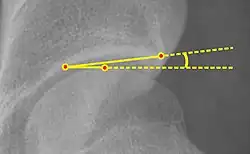

- Reimer's migration index (MI), also called the femoral extrusion index,[3] is calculated if hip dysplasia is detected. It can be used to indicate hip dislocation. It is the horizontal distance (parallel to the Hilgenreiner Line) between the Perkin line and the lateral border of the ossification center of the femoral head, divided by the horizontal width of the ossification center. The migration index is normally less than 33% by most sources,[9] but 25% and 30% has also been suggested.[10]

| Reimer's migration index[9] |

|

The percentage of the femoral head that lies outside of the acetabular roof. It is also called the femoral extrusion index. | <25% |